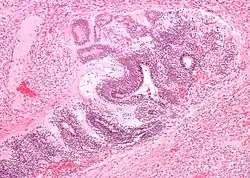

| Micrograph of the primitive neuroepithelium of an immature teratoma of the mediastinum. H&E stain. | |

A mediastinal tumor is a tumor in the mediastinum, the cavity that separates the lungs from the rest of the chest. It contains the heart, esophagus, trachea, thymus, and aorta. The most common mediastinal masses are thymoma (20% of mediastinal tumors), usually found in the anterior mediastinum, followed by neurogenic Timor (15–20%) located in the anterior mediastinum.[1] Lung cancer typically spreads to the lymph nodes in the mediastinum.

The mediastinum has three main parts: the anterior mediastinum (front), the middle mediastinum, and the posterior mediastinum (back). Masses in the anterior portion of the mediastinum can include thymoma, lymphoma, pheochromocytoma, germ cell tumors including teratoma, thyroid tissue, and parathyroid lesions. Masses in this area are more likely to be malignant than those in other compartments.[2][3]